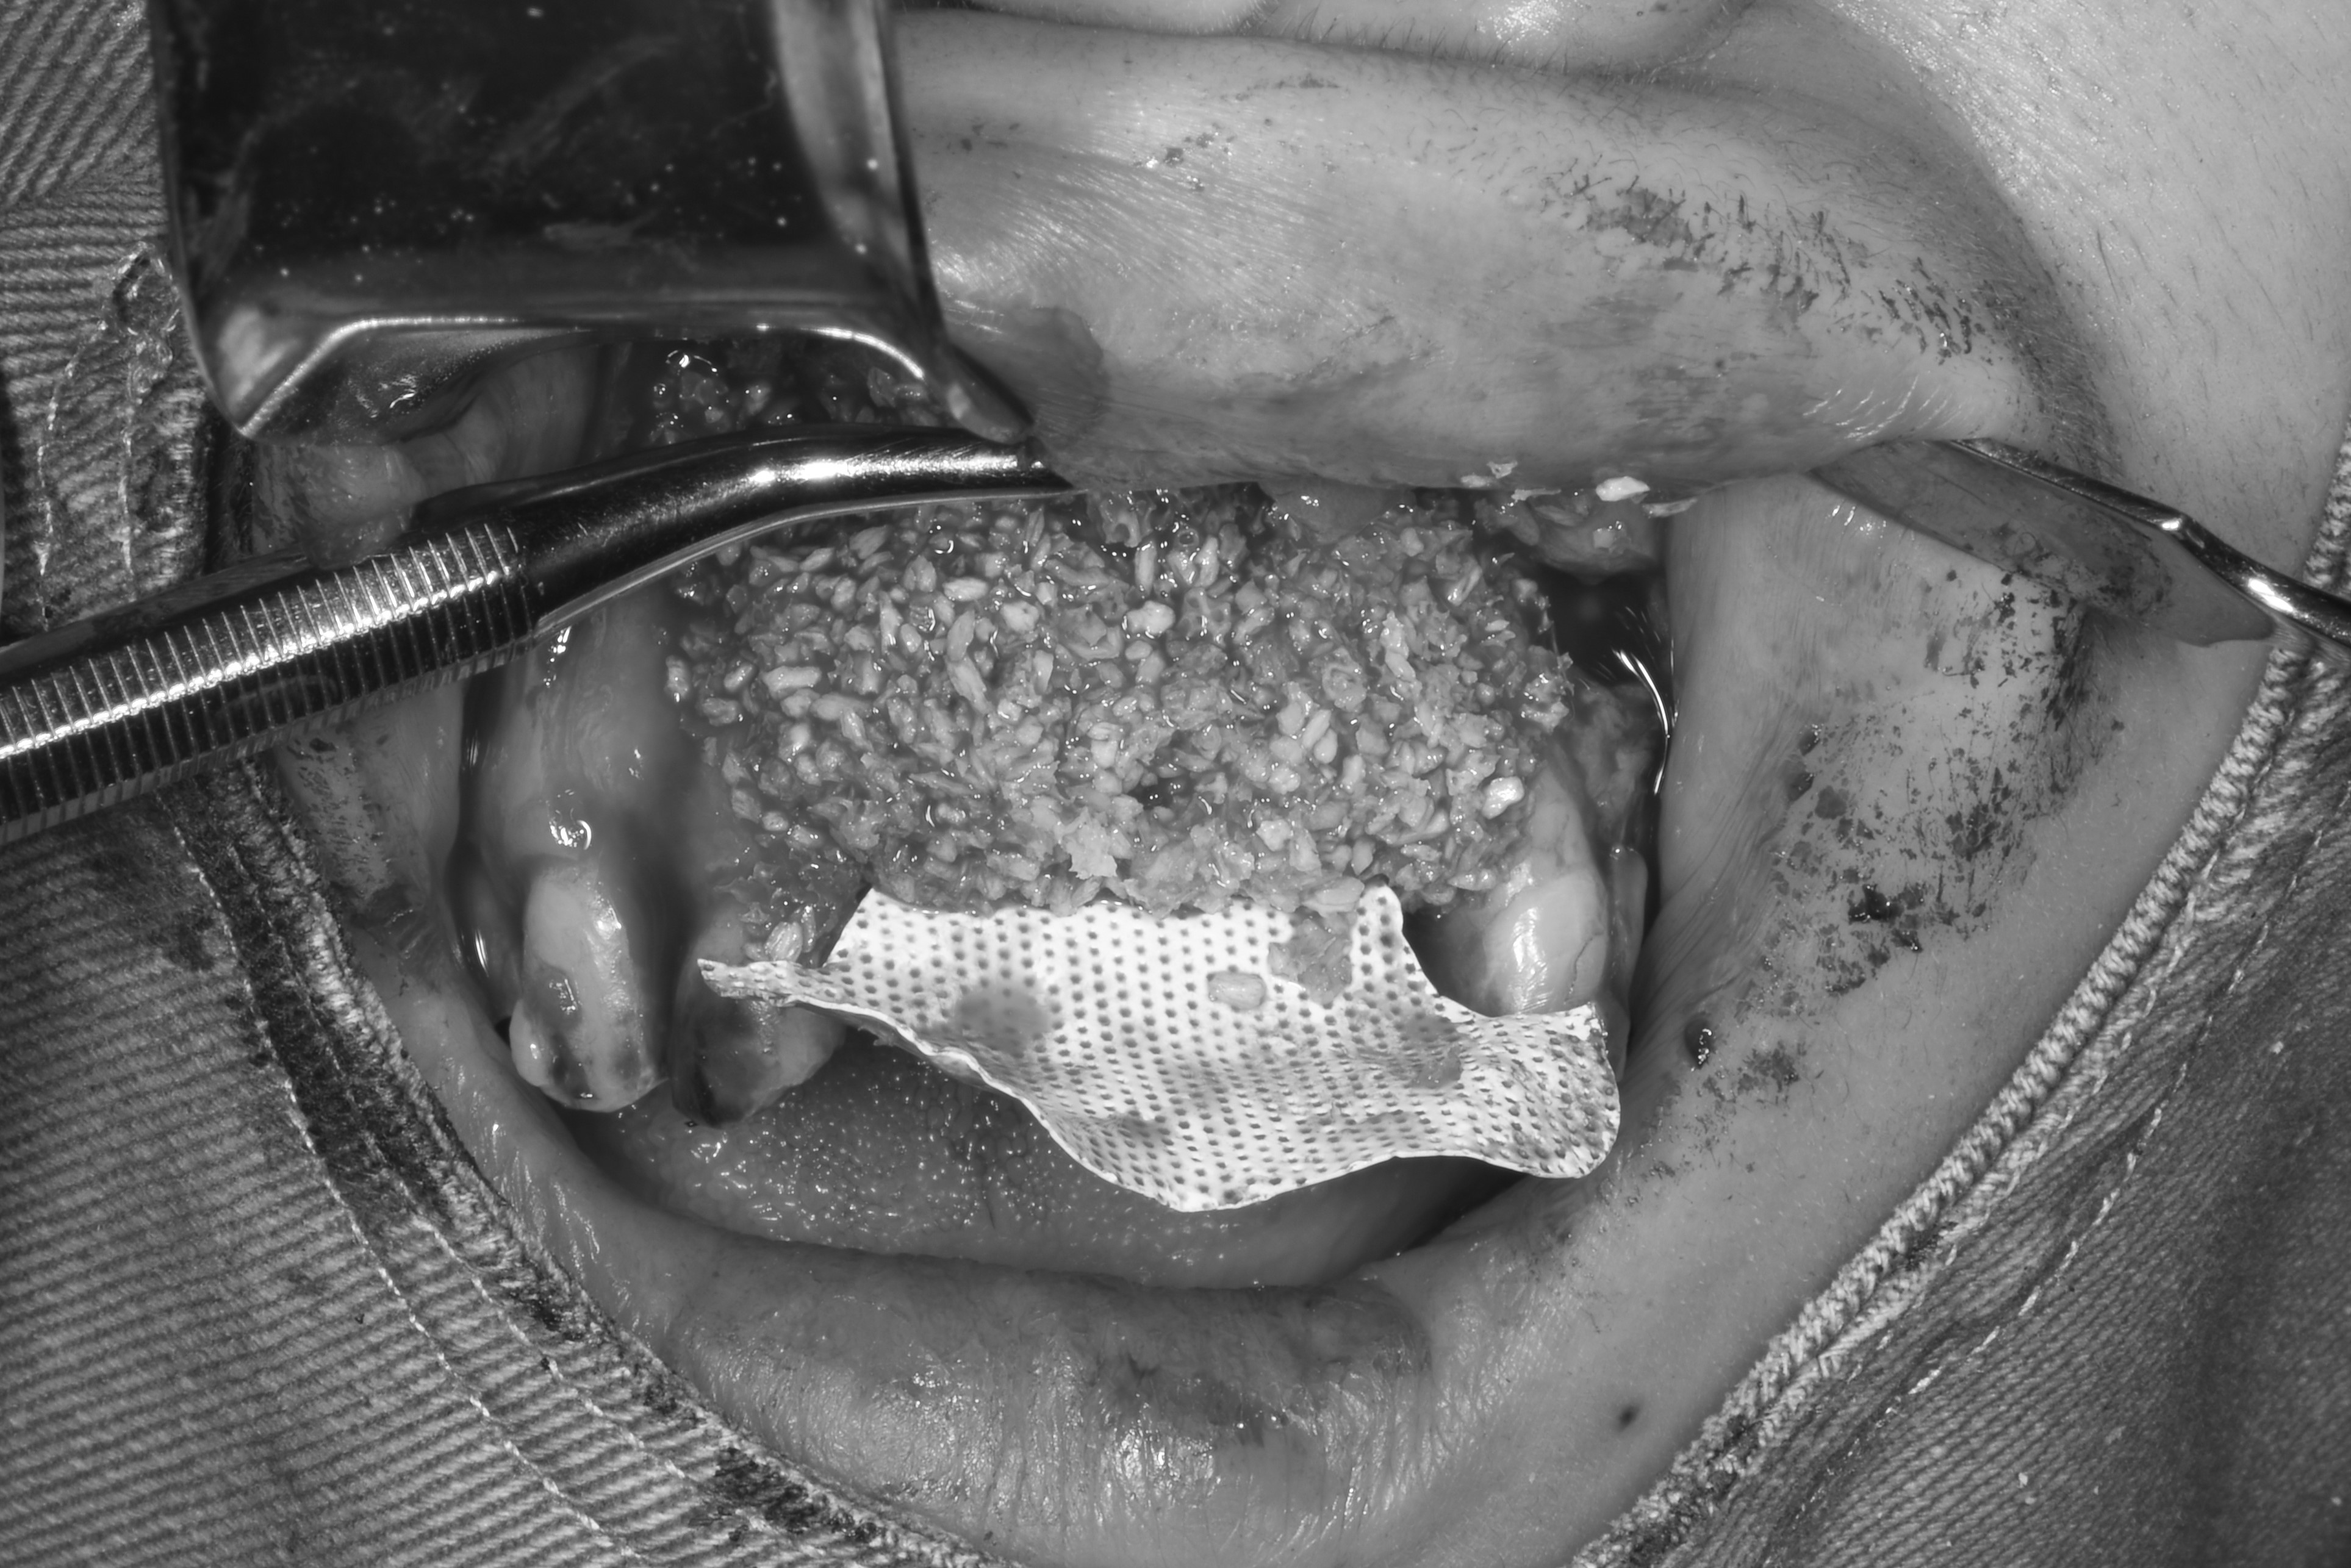

案例三

缺牙太久造成齒槽骨大量流失

先放入不可吸收骨膜,增加骨頭高度與面積

*不可吸收骨膜:不會被身體吸收、需要再開刀取出的膜,放在補骨區用來隔離軟組織並撐住空間,讓骨粉有足夠時間生長成新骨

補入所需骨粉

蓋上可吸收骨膜

*可吸收骨膜:會被身體自然吸收、不需再開刀取出的骨膜,用在補骨手術中,主要功能是隔離軟組織、保護骨粉、協助骨再生

最後縫合傷口,等待癒合

明顯看到補骨的高度